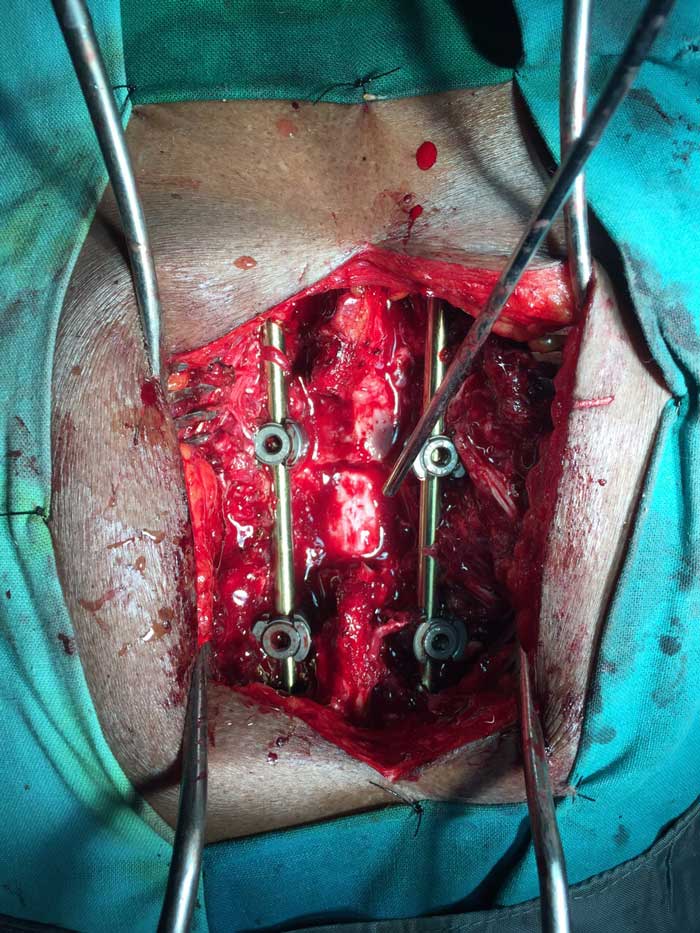

INTRA OP SPINE FIXATION

Spine Fixation Lumbar Spine